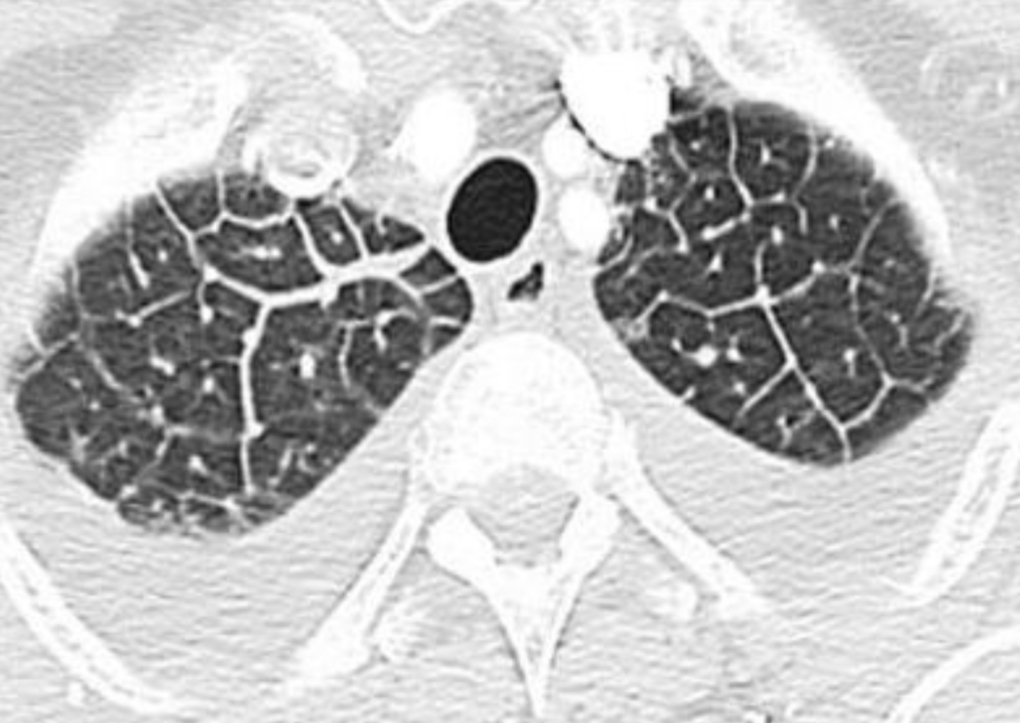

def: Es una estructura anatómica que se ve en la tomografía, divido en septos interlobulillares

A

lobulillo pulmonar secundario

Este patron pulmonar ocurre por ocupación o enfermedad del intersticio, dando una forma de “red” o “telaraña” con pequeños puntos en el centro

¿Cómo se ve el patrón intersticial/reticular en TC y RX?

RX: líneas finas o gruesas que se ven en los extremos del pulmón

TC: Líneas finas o gruesas